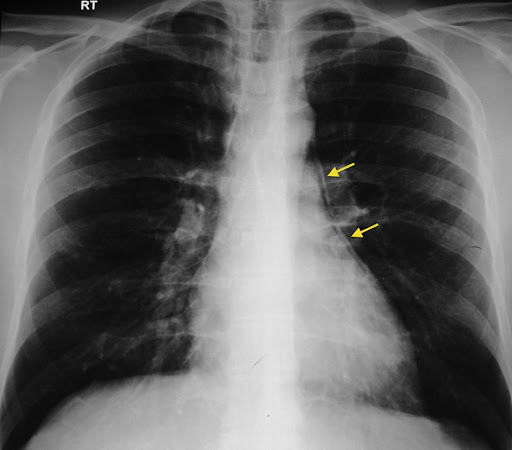

Рентгенография выявляет следующие признаки пневмомедиастинума:

Полосы или просветления линейной формы, окружающие контуры средостенных структур (трахеи, пищевода, аорты, сердца), сигнализирующие о скоплении свободного газа.

Чёткая визуализация границ крупных сосудов и сердца, которые в норме не прослеживаются так отчётливо, за счёт оконтуривания их воздухом.

Воздушные полосы, распространяющиеся в мягкие ткани шеи, надключичные области или корни лёгких, отражающие распространение газа из средостения.